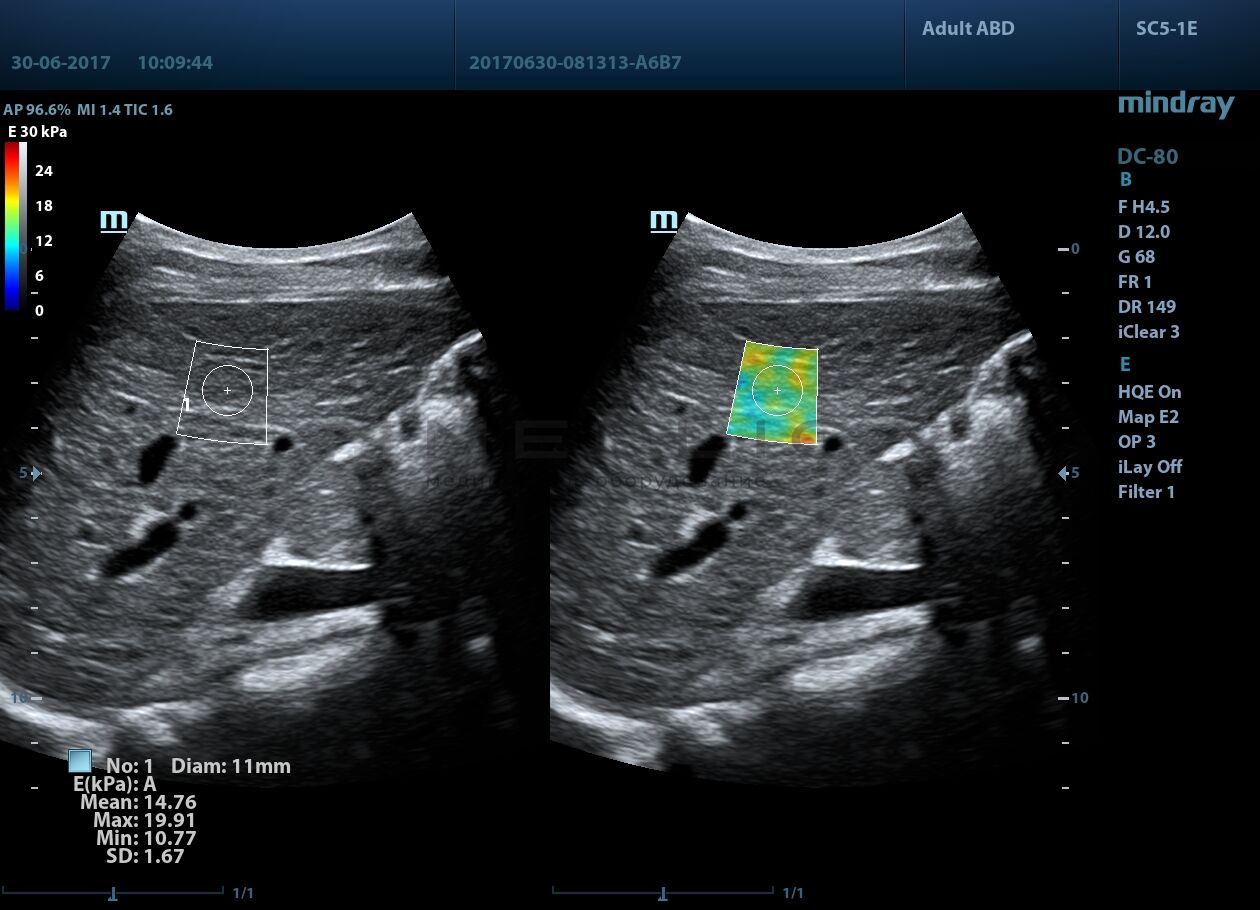

Программное обеспечение для оценки эластичности ткани методом эластографии сдвиговой волны (метод 2D-с формированием двухмерной цветовой эластограммы и количественной оценкой эластичности) на линейных и конвексных датчиках.

STE интегрирована с эксклюзивной технологией Ultra-Wide Beam Tracking от Mindray для двумерной эластографии сдвиговой волной в реальном времени. Специализированные измерительные инструменты позволяют проводить количественный анализ модуля упругости с высокой точностью.